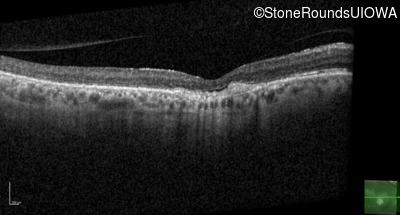

Optical Coherence Tomography - Right - 20/80

Exemplar / OCT Stack

OCT Stack

Optical Coherence Tomography - Left - 20/125